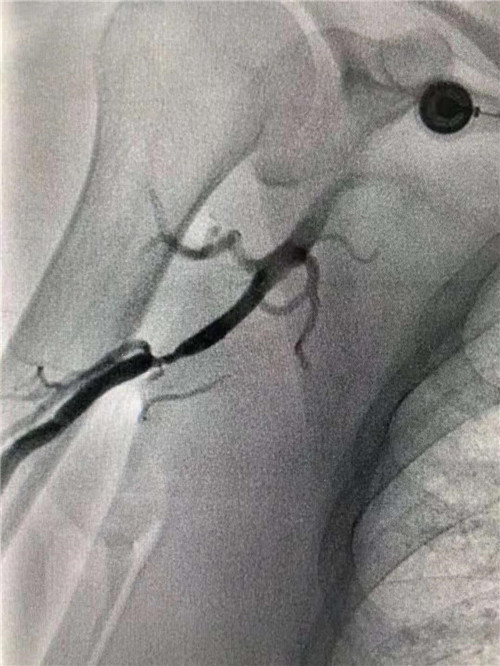

右側(cè)肱動脈重度狹窄

快速完成右側(cè)橈動脈穿刺,上造影導(dǎo)管受阻后,行肱動脈造影,發(fā)現(xiàn)右側(cè)肱動脈重度狹窄。